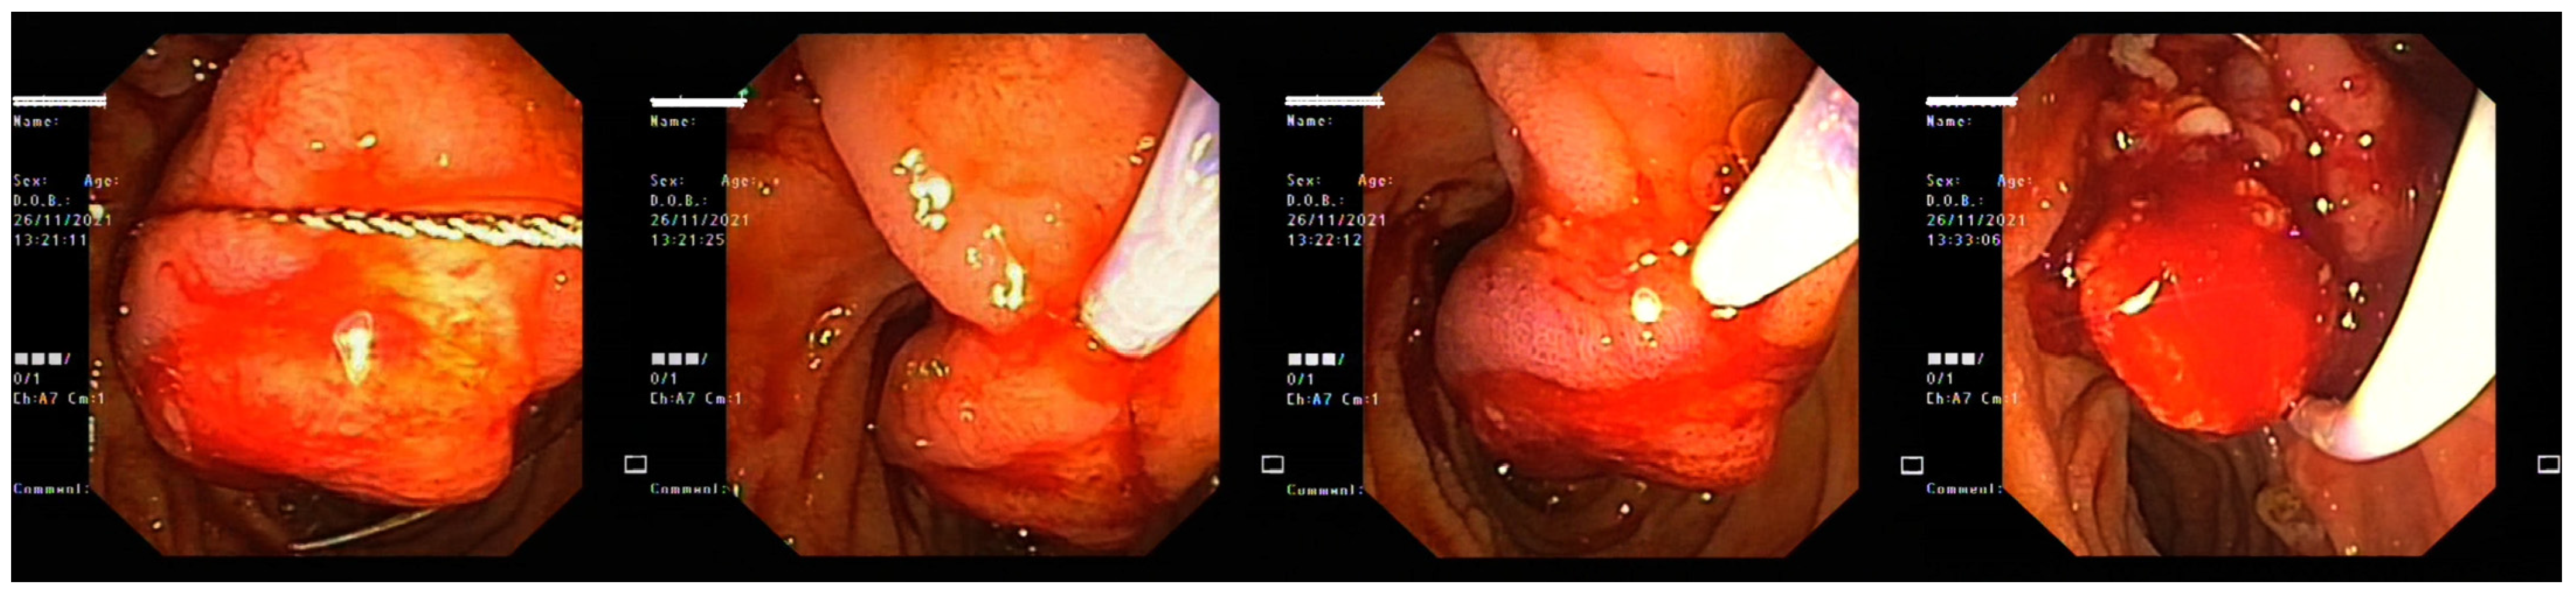

3. Case Report 2